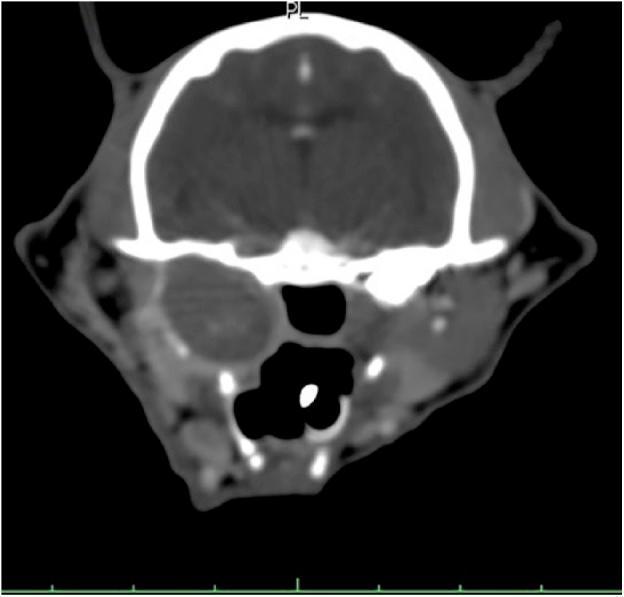

A 14-year-old neutered female Burmese cat was referred for investigation of a caudal oropharyngeal mass. CT showed a thin walled cyst-like structure filling and expanding from the right tympanic bulla. Histopathology showed fragments of mildly dysplastic squamous epithelium and aggregates of keratin. These findings were considered consistent with a diagnosis of cholesteatoma.

一只14岁已绝育的缅甸母猫因尾侧口咽部肿物接受检查。CT显示一个薄壁囊肿样结构,从右鼓室填充并扩张。组织病理学显示轻度发育异常的鳞状上皮碎片和角蛋白聚集体。这些发现被认为与胆脂瘤的诊断一致。